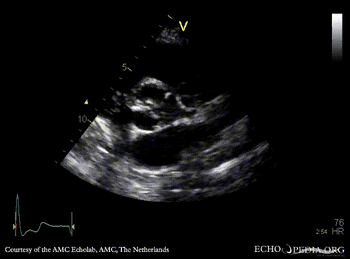

Severe aortic valve stenosis and plaque in abdominal aorta

PLAX: concentric hypertrophy of left ventricle, thickend aortic valve PSAX: concentric hypertrophy of left ventricle